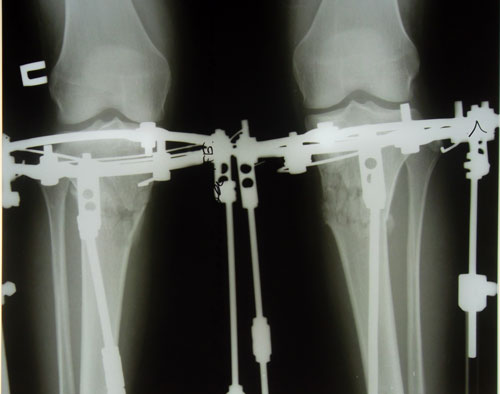

- Диагноз: кривые ноги

Ноги постепенно выравниваются.настроение отличное!

Наташа здраствуйте! вы результат рентгена не сообщили? С нетерпением жду. Заранее спасибо!